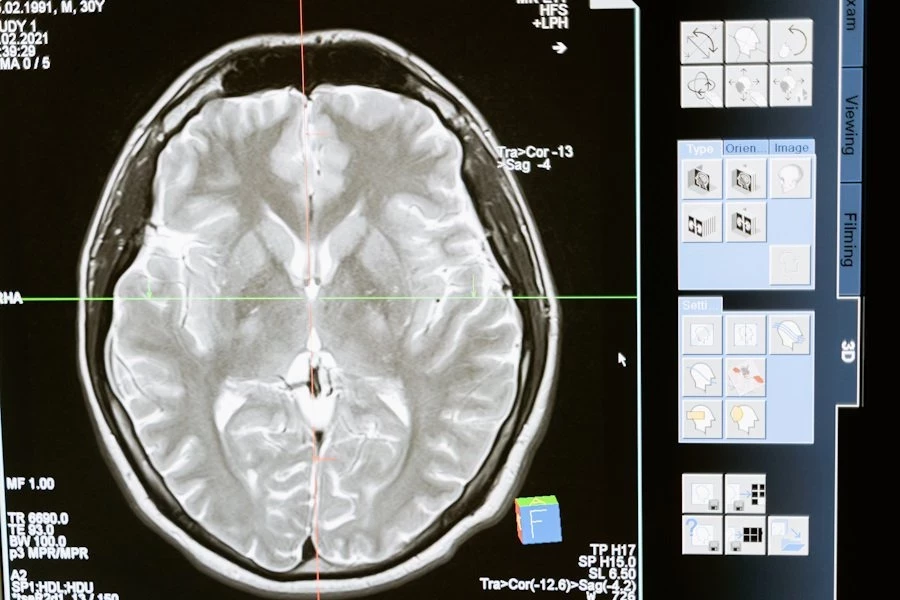

Учёные Fudan University (КНР) свершили прорыв в понимании старения мозга: исследование, опубликованное на портале Nature, выявило 13 белков, которые могут стать маркерами биологического возраста мозга. Эти белки, обнаруженные в плазме крови, связаны с процессами стресса, воспаления и регенерации, а их концентрация достигает пиков в определённые возрастные периоды: 57, 70 и 78 лет.

Для анализа использовались данные визуализации мозга 10 949 человек в возрасте от 45 до 82 лет и образцы крови почти 5 000 участников. Учёные также подтвердили причинно-следственную связь между уровнем BCAN и ускоренным старением мозга с помощью генетического метода Менделевской рандомизации.